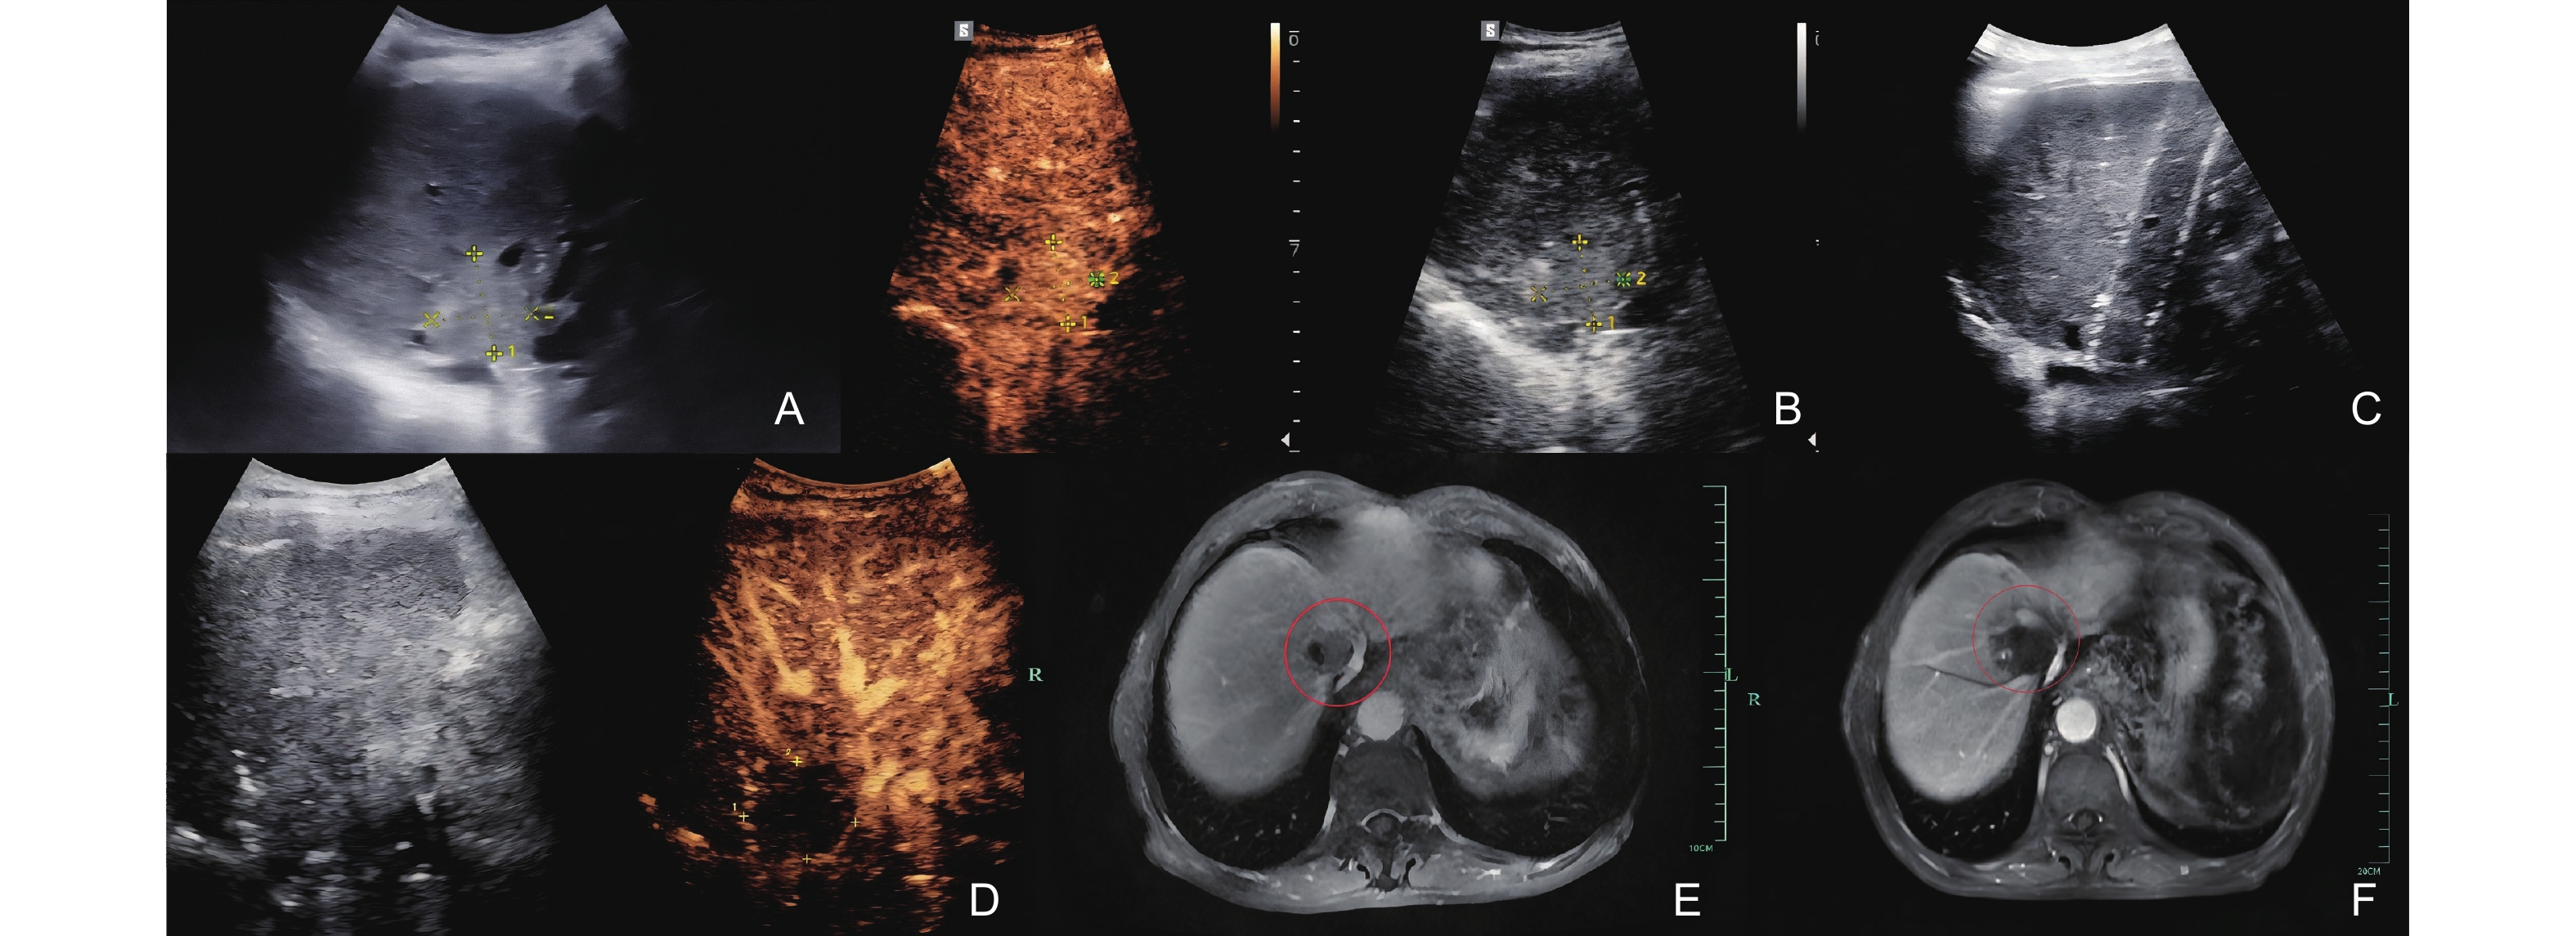

Figure 1

A 66-year-old male patient with a history of “liver cancer and hepatitis B cirrhosis” underwent liver transplantation in 2022. One year later, the liver cancer recurred, despite undergoing TACE, radiotherapy, and targeted therapy, the lesion remained active, leading to IRE treatment. (A) The US lesion prior to surgery was approximately 31×30 mm, located at the second porta hepatis; (B) The lesion showed rapid enhancement at the 20th second during preoperative contrast-enhanced ultrasound (CEUS); (C) Two ablation needles were used during the lesion ablation procedure; (D) Immediate CEUS after ablation showed no significant enhancement of the lesion. MRI imaging during the venous phase showed an abnormal signal focus in segment S7 with unclear boundaries; (E) Preoperative; (F) One month post-surgery."